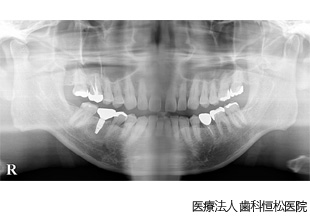

【症例2】下顎All-on-4治療

- 治療前

- 治療後

- 治療名

- 下顎All-on-4治療

- 費用

- 2,816,000円(税込)

- 期間

- 6ヵ月

治療内容

患者様の症状

上下顎に重度の歯周病が進行し、無歯顎となった患者様。上顎は義歯を問題なく使用できていたが、下顎は義歯使用に対する違和感が強く、インプラント治療を希望。

治療法

最終的な歯の形や位置を想定してシミュレーションを行い、専用のガイド(サージカルステント)を作製。ガイドを使用してインプラントを適切な位置に植立。植立後、約3ヵ月で仮歯を装着し、清掃性、審美性、噛み合わせのバランスを確認。その後、問題がないことを確認して最終的な人工歯を装着。

治療結果

機能性・審美性ともに良好に回復。

※治療結果は患者様によって個人差があります。